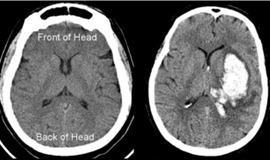

A hemorrhagic stroke accounts for the remaining 13% of stroke cases (American Stroke Association, 2024). This is when a blood vessel ruptures (bursts), leading to bleeding in the brain. Intracerebral hemorrhage is when the bleed is within the cortex. Subarachnoid or epidural hemorrhage is when the bleed is between the brain and its coverings (meninges).

Figure 1. The right image shows a normal CT scan of the brain. The left image shows an intracerebral hemorrhagic stroke on the [patient’s] left hemisphere. This can be seen in the bright white spot, which is the blood from the ruptured blood vessel.